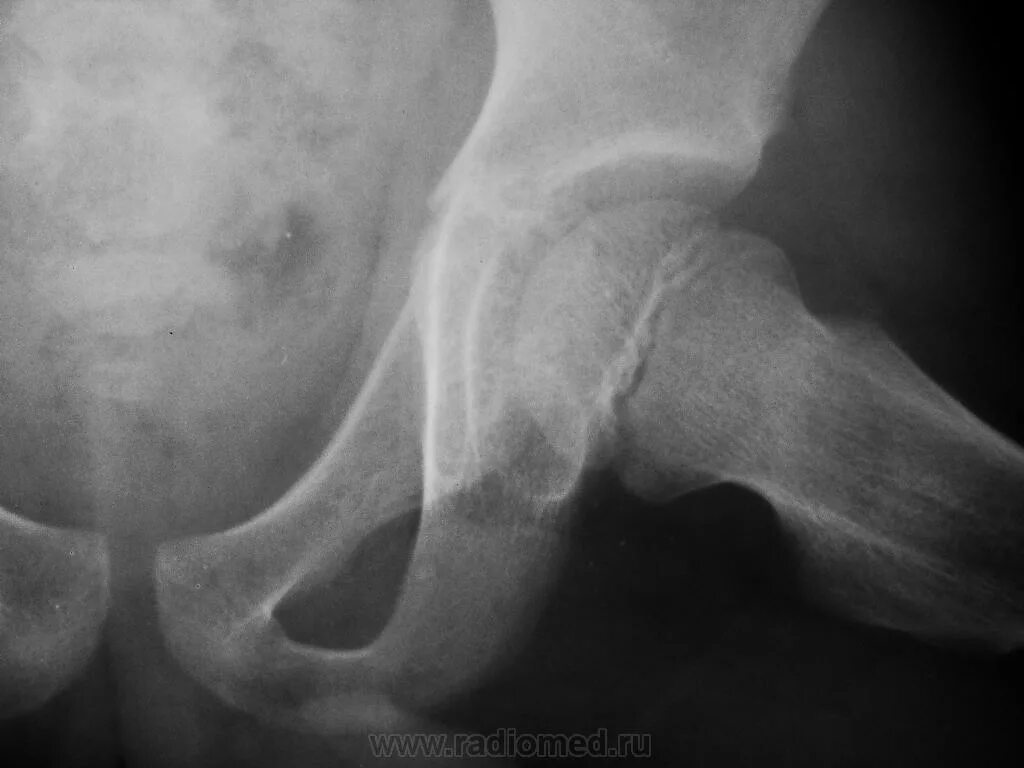

Рентгенограмма тазобедренного сустава